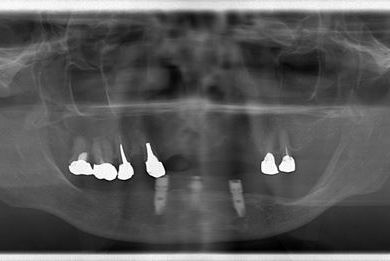

インプラントの症例写真 IMPLANT

インプラント治療+オーバーデンチャー

| 治療方針 | 下顎に2本インプラントを埋入し、アタッチメントをつけて、オーバーデンチャーを装着し、はずれにくく、安定した義歯を装着する。 | ||||||||||||||||||||||||||||||||

| 治療内容 | インプラント2本(テンポラリーインプラント)、アタッチメント、コバルトクロム床オーバーデンチャー | ||||||||||||||||||||||||||||||||